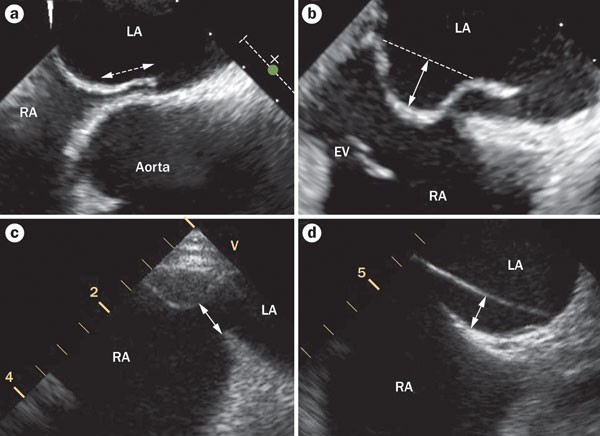

open pfo sale